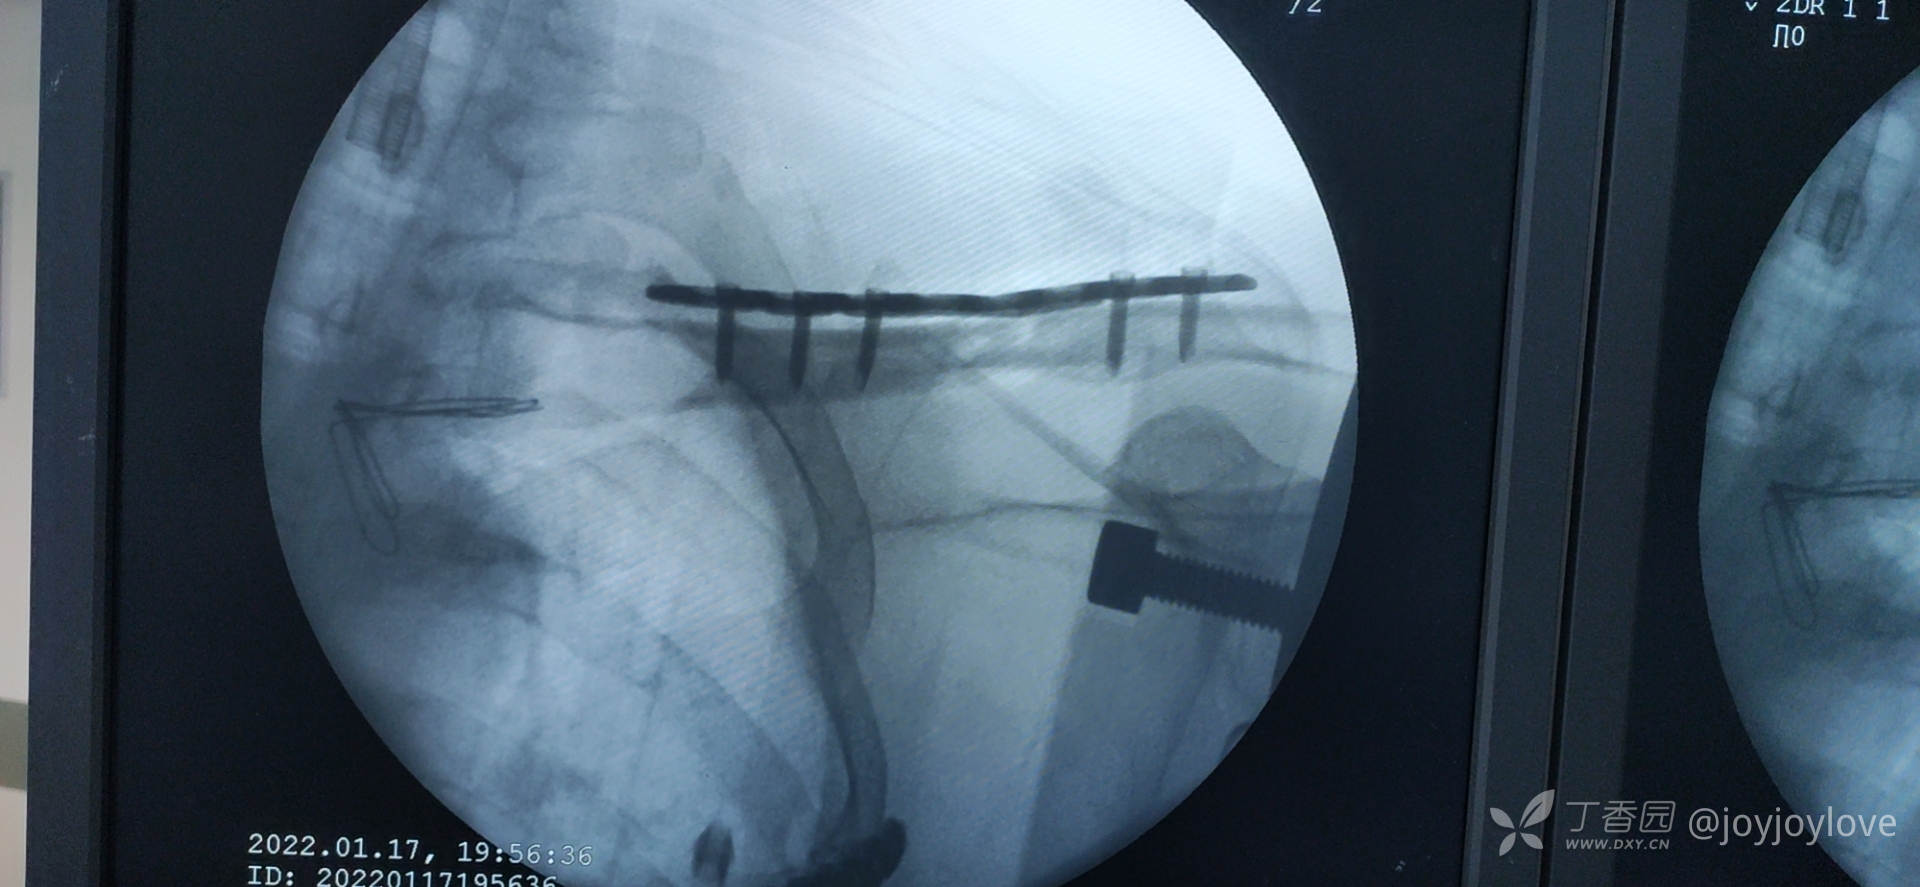

病例备忘录:2022锁骨

曹谦湘潭市中医院 等 3 位达人已点赞左侧锁骨中段骨折。

1.器械包里没有备折弯器械,用老虎钳折弯,费劲

2.术前备好的板子,角峰板子被器械护士开包装时好掉在地上,再用,需要至少消毒3小时…心塞

3.中段蝶形骨块,长斜块,3块骨折线,企图一枚拉力螺钉,结果拉力螺钉顶着皮质进,把骨折线顶开了,换成2枚拉力螺钉固定。